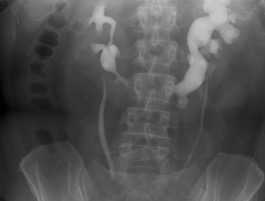

Внутривенная урография. Подковообразная левая почка.

План диагностического обследования включает УЗИ, УЗДГ, экскреторную урографию либо ретроградную пиелографию, почечную артериографию, сцинтиграфию, компьютерную томографию. Урограммы позволяют рассмотреть низкое расположение органа, ограниченную подвижность, наслоение теней нижних полюсов почки на контур позвоночного столба, тень перешейка. При ретроградной пиелографии в первые минуты визуализируется четкий силуэт подковообразной почки и ее перешейка, низкое положение почечных лоханок, аномальное расположение чашечек.

В процессе УЗИ почек может быть выявлено нетипичное расположение почечных лоханок, аномальная форма чашечек, при допплерографии обнаруживается аномальное кровоснабжение такой почки. Урография позволяет определить нетипичное расположение органа, тень перешейка и наслоение тканей почки на контур позвоночного столба. Ретроградная пиелография позволяет визуализировать подковообразную форму почки пациента и различные аномалии анатомического строения почки.